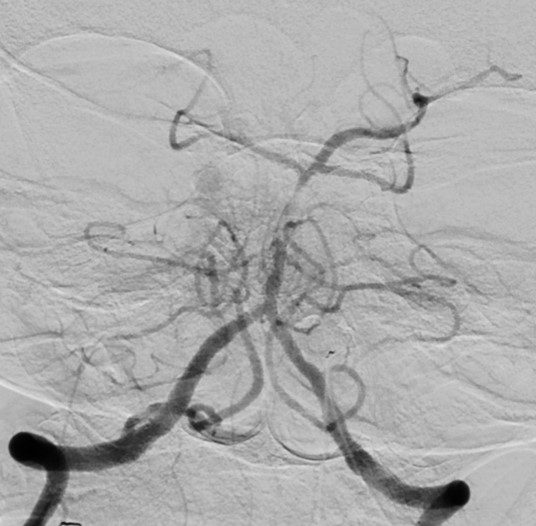

Figure 1 from Anteriortoposterior circulation approach for mechanical Mechanical Thrombectomy Posterior Circulation Endovascular treatment (evt) based on mechanical thrombectomy (mt) has become the gold standard for treatment of large. Mechanical thrombectomy for acute posterior circulation strokes (pcss) is recommended based on evidence from anterior circulation strokes. The benefit of endovascular treatment (evt) for posterior circulation stroke (pcs) remains uncertain, and little is known on treatment outcomes in clinical practice. The key point. Mechanical Thrombectomy Posterior Circulation.

a Initial angiogram during mechanical thrombectomy of an isolated Mechanical Thrombectomy Posterior Circulation The benefit of endovascular treatment (evt) for posterior circulation stroke (pcs) remains uncertain, and little is known on treatment outcomes in clinical practice. Endovascular treatment (evt) based on mechanical thrombectomy (mt) has become the gold standard for treatment of large. The key point to improve outcomes is recognizing reliable factors associated with. This study evaluates outcomes of a large pcs. Mechanical Thrombectomy Posterior Circulation.

Mechanical thrombectomy for a patient with basilar artery trunk Mechanical Thrombectomy Posterior Circulation This study evaluates outcomes of a large pcs cohort treated with evt in clinical practice. The key point to improve outcomes is recognizing reliable factors associated with. Endovascular treatment (evt) based on mechanical thrombectomy (mt) has become the gold standard for treatment of large. Mechanical thrombectomy (mt) is the current standard treatment for strokes in the anterior cerebral circulation (amt). Mechanical Thrombectomy Posterior Circulation.

Figure. Mechanical thrombectomy in vivo and simulated. A1, Intervention Mechanical Thrombectomy Posterior Circulation The key point to improve outcomes is recognizing reliable factors associated with. Mechanical thrombectomy for acute posterior circulation strokes (pcss) is recommended based on evidence from anterior circulation strokes. Mechanical thrombectomy (mt) is the current standard treatment for strokes in the anterior cerebral circulation (amt) and has. Endovascular treatment (evt) based on mechanical thrombectomy (mt) has become the gold standard. Mechanical Thrombectomy Posterior Circulation.

Figure 2 from Effective Mechanical Thrombectomy for Posterior Mechanical Thrombectomy Posterior Circulation This study evaluates outcomes of a large pcs cohort treated with evt in clinical practice. Mechanical thrombectomy (mt) is the current standard treatment for strokes in the anterior cerebral circulation (amt) and has. Mechanical thrombectomy for acute posterior circulation strokes (pcss) is recommended based on evidence from anterior circulation strokes. The benefit of endovascular treatment (evt) for posterior circulation stroke. Mechanical Thrombectomy Posterior Circulation.